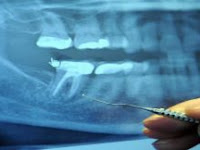

97% of Terminal Cancer Patients Had This Dental Procedure

97% of Terminal Cancer Patients Had This Dental Procedure - Believe it or not, the main reason for the serious disease you’ve been struggli...